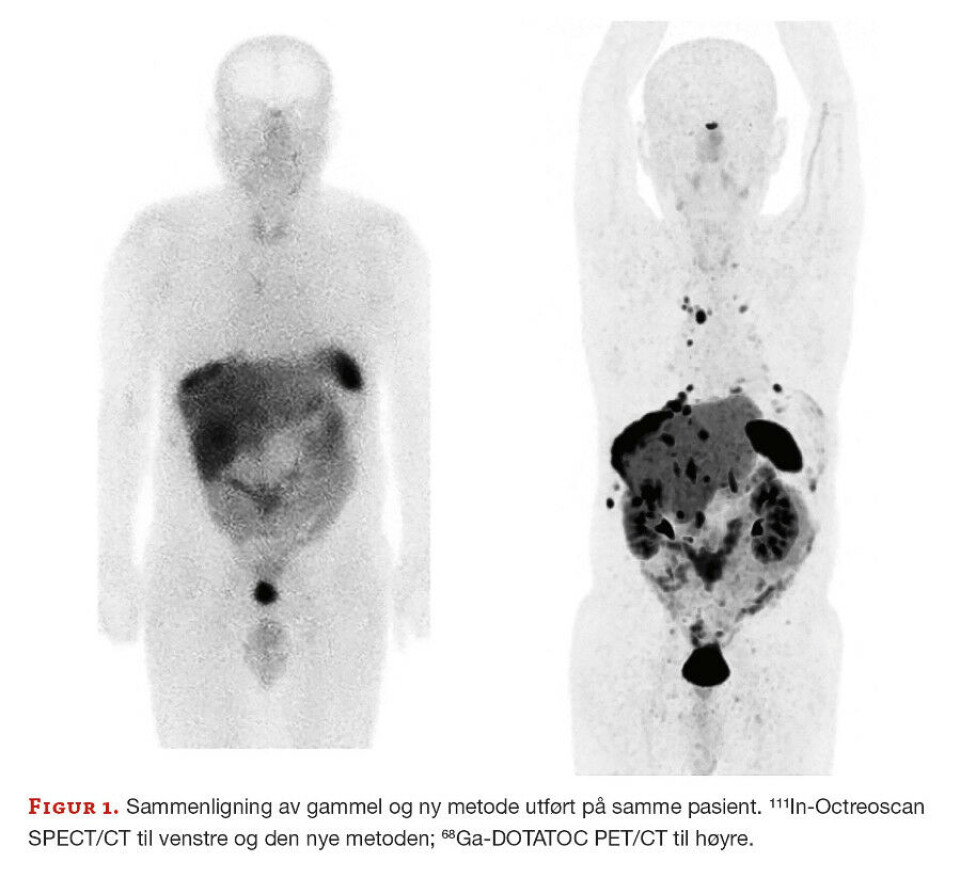

Den nye undersøkelsesmetoden er betraktelig bedre med høyere spesifikk bindingsevne til reseptorer på celleoverflaten i svulstvevet. PET-skannere er i tillegg over 10 ganger mer følsomme enn SPECT-skannere (figur 1).

Etableringen av 68Ga-DOTATOC PET/CT har vært en lang prosess. Vi har hatt nytte av å hospitere ved Senter for nukleærmedisin/PET på Haukeland Universitetssjukehus (som etablerte metoden høsten 2017), samt deltakelse på Europeisk kongress i Nukleærmedisin (Düsseldorf, høst 2018) hvor vi så på nødvendig utstyr fra ulike leverandører. I tillegg har vi jobbet tett med leverandøren av generatoren for praktisk tilrettelegging og opplæring. De var også til stede under vår første pasientundersøkelse. Bildene vi nå fremstiller på PET/CT-skanneren er av høy kvalitet, og de kan knapt sammenlignes med bildene kjørt etter gammel metode med SPECT/CT.